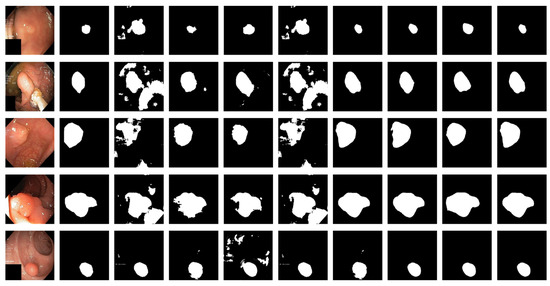

Figure 6 shows the qualitative results for all models. Figure 7 shows the highlighting of TN, TP, FP, and FN by assigning different colors to the pixels of each category, where TN is black, TP is white, FN is red, and FP is blue. In Table 3 and Figure 6, the advantages of the PRAPNet over the baseline architectures are shown. The quantitative and qualitative results all show that the PRAPNet model trained on the Kvasir-SEG dataset showed satisfying results and transcended the other seven models in terms of the dice coefficient, mIoU, and precision. Therefore, in the task of medical image segmentation, the PRAPNet architecture has obvious advantages over the other segmentation methods.

Figure 6.

Comparison of qualitative results from the Kvasir-SEG dataset. From left to right are the image, the mask, and the segmentation results of unet, U-Net++, ResUNet++, praNet, SFFormer-L, TransFuse-L, CaraNet, and PRAPNet.

The PRAPNet architecture proposed in this paper achieved satisfactory results from the Kvasir-SEG dataset. From Figure 6, it could be concluded that, from the Kvasir-SEG dataset, the segmentation maps generated by the PRAPNet outperformed the other architectures in capturing the shape information, demonstrating that the segmentation masks generated in the PRAPNet showed more precise information in the target area than the existing models. The full convolutional network has room for improvement in capturing the polyp location and edge details.